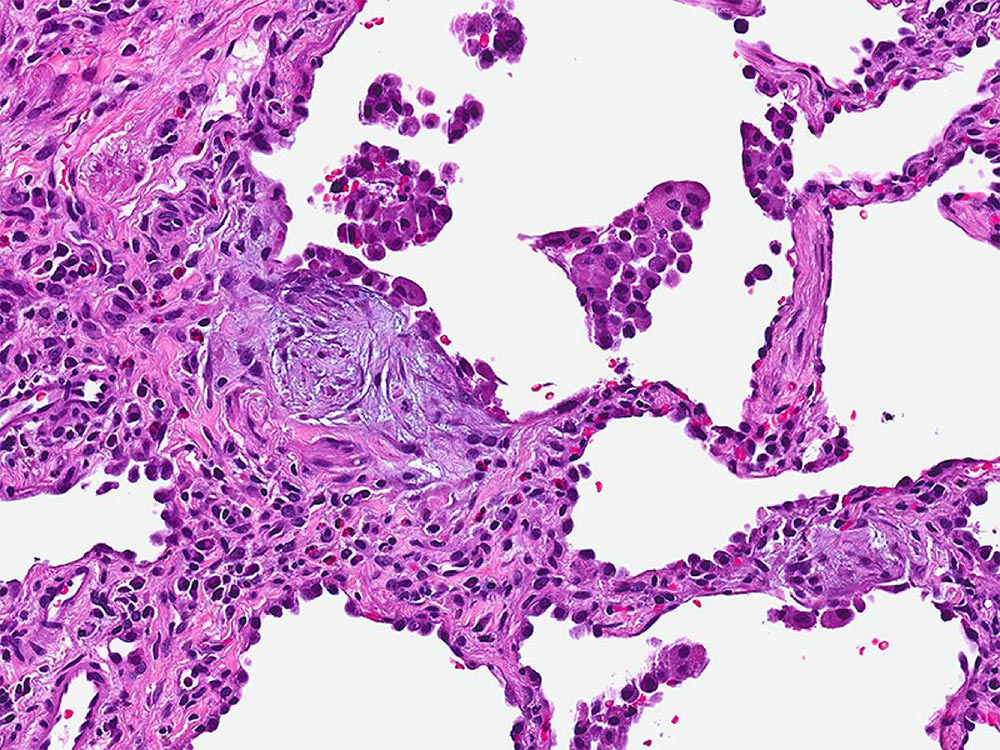

High magnification photomicrograph illustrating a fibroblast focus in a patient with usual interstitial pneumonia (UIP). Fibroblast foci are comprised of proliferating fibroblasts and myofibroblasts and are a consistent finding in UIP.

Image courtesy of and used with permission from Kirk Jones, MD.